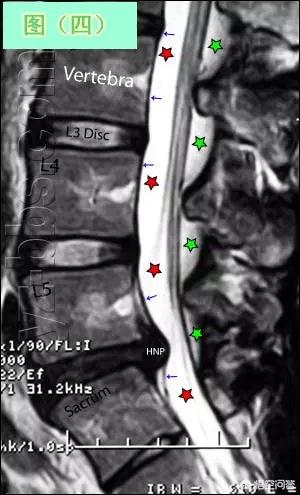

臨床では、症状が消失していなくても、脱水や自己陶酔に由来する原因不明で隆起が低下する人がおり、受傷直後に受診した人にこの問題が多いことが観察されており、通常は6ヶ月以内の適時治療と安静が隆起を低下させる確率が高い。

フィルムが小さくなる人